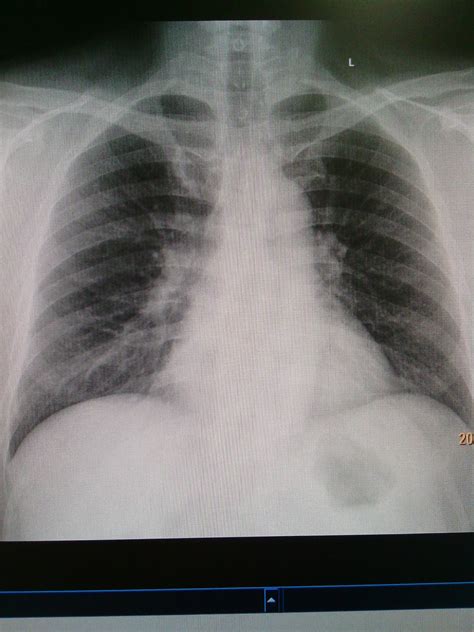

A bronchitis X ray is a crucial diagnostic tool that helps healthcare providers visualize the lungs and bronchial tubes. This imaging technique uses X-rays to create detailed images of the chest, allowing doctors to identify any abnormalities or inflammation. The bronchitis X ray can reveal:

• Inflammation and swelling of the bronchial tubes

• Presence of mucus or fluid in the lungs

• Signs of infection or pneumonia

• Structural abnormalities in the lungs

Interpreting Bronchitis X Ray Results

Interpreting the results of a bronchitis X ray requires the expertise of a radiologist or healthcare provider. The images are carefully examined for signs of inflammation, infection, or other abnormalities. Key findings that may be noted include:

• Increased density or opacity in the lungs, indicating inflammation or fluid buildup

• Thickening of the bronchial walls

• Presence of nodules or masses

• Signs of pneumonia or other respiratory infections

Based on the findings, the healthcare provider will develop a treatment plan tailored to the patient's specific needs. This may include medications, lifestyle changes, or further diagnostic tests.